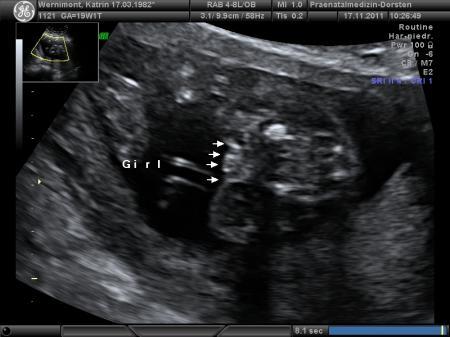

Antwort auf Beitrag von Jasmin686

Das war unser Outing-Bild

Bild zu